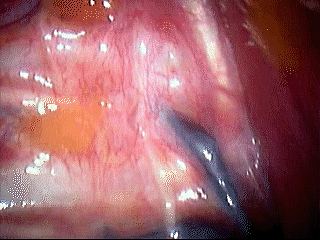

Surgical techniques: General anesthesia is used, including one lung ventilation with a double lumen endobronchial tube. CO2 insufflation is used to help induce lung collapse. A semi-Fowler's position is preferred with the patient's arms abducted and a roll behind the shoulders to improve access to the upper sympathetic chain (Figure 1). With gravity the lung naturally falls downwards and away from the upper posterior chest wall. Only one 7mm or 10mm port with an operative-thoracoscope is needed for manipulation. Alternatively, one telescope port and one operating port are placed if an operating thoracoscope is not available. The sympathetic chain is easily identified under the parietal pleura, running vertically over the necks of the ribs in the upper costo-vertebral region.

We perform bilateral synchronous sympathectomy starting on the right side. An L-shaped hook cautery alternating cutting/coagulation is used to divide the sympathetic chain as this is easier and quicker than attempting to remove a segment of the chain (Figures 2-4). Special care is taken to make sure that complete ablation of ganglia and severance of the sympathetic chain is achieved. We generally continue the dissection by cauterizing/dividing the pleura for 5 cm lateral to the chain. If an aberrant nerve bundle of Kuntz is identified, it too is severed. The transected ends of the sympathetic chain are separated as far as possible and cauterized to prevent regrowth of the nerve and recurrence of symptoms. For patients with hyperhidrosis, level T2 and T3 or T2-T5 are divided, depending on the severity of the lower extremity symptoms. Care should be taken not to divide the sympathetic chain above the level of the second rib for the treatment of palmar and plantar hyperhidrosis, because it increases the risk of Horner's syndrome and contributes little benefit. Thoracic outlet syndrome or reflex sympathetic dystrophy is usually approached at T1-T3. For chronic pancreatic pain, we usually divide the sympathetic chain at the level of T4 to T10. Before closing the skin, a small chest tube is left in the chest and the subcutaneous tissue is closed with 3-0 Vicryl. After expanding both the patient's lungs with positive pressure ventilation, the tube is removed from the chest quickly at positive pressure to avoid a residual pneumothorax, and then a final subcuticular suture is placed. Hence, no thoracic drain is needed postoperatively. The procedure is then repeated on the left side. A chest radiograph is immediately obtained after the operation in the operating room to ensure complete lung expansion. The operation is usually performed in an outpatient setting, and patients are discharged 6-8 hours after the operation.